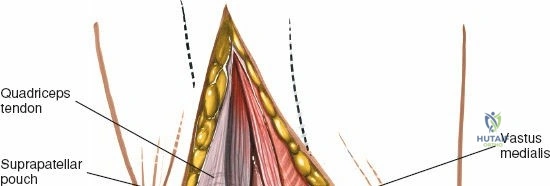

The extensor mechanism comprises the quadriceps femoris muscle group, the quadriceps tendon, the patella, the patellar tendon (ligament), and its insertion into the tibial tubercle.

* Quadriceps Tendon: The confluence of the rectus femoris, vastus lateralis, vastus medialis, and vastus intermedius. The medial parapatellar approach involves an incision extending into the medial aspect of the quadriceps tendon or a separation between the vastus medialis and rectus femoris.

Deep to the extensor mechanism lies the joint capsule, which is continuous with the periosteum of the distal femur and proximal tibia. The capsule forms the suprapatellar pouch proximally, a crucial area for exposure and débridement. The synovial membrane lines the inner surface of the capsule and extends into the joint, forming the intra-articular fat pad (Hoffa's fat pad) distal to the patella.

* The incision through the joint capsule and retinaculum begins proximally, extending through the medial aspect of the quadriceps tendon.

* It then follows the border between the vastus medialis obliquus (VMO) and the patella, curving distally along the medial border of the patella.

* The incision continues distal to the patella, medial to the patellar tendon, into the synovium and capsule.

* The extent of the proximal and distal incision depends on the required exposure. For TKA, it is typically extended well into the quadriceps tendon proximally and to the tibial tubercle distally.

The medial retinaculum and vastus medialis obliquus are exposed. The proposed capsular incision along the medial patellar border is outlined.